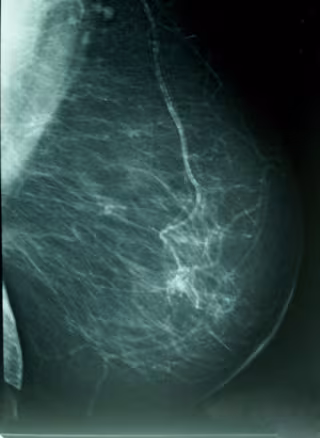

Cáncer De Mama, Densidad Mamográfica

La clave de esta supervivencia es la implantación de programas de cribado en todas las comunidades mediante la realización de mamografías a partir de los 40-45 años y del buen cumplimiento de las mujeres españolas.